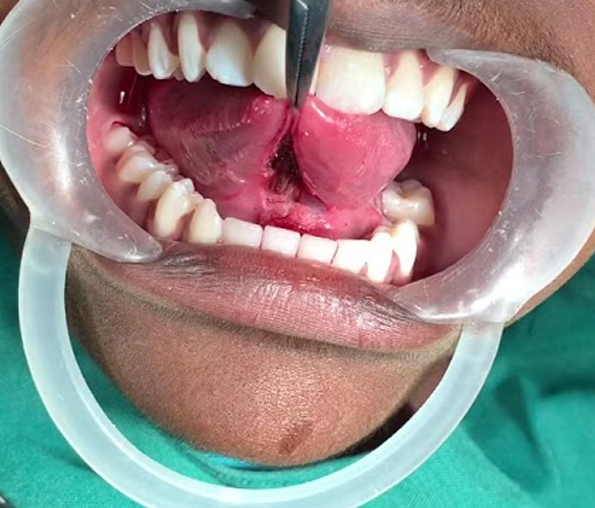

Oral Cancer

image